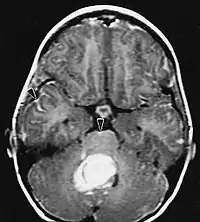

Na ressonância magnética, um tumor intracraniano aparece como uma lesão maciça que pode se tornar mais luminescente após o uso do agente de contraste. No entanto, há sempre uma anomalia de sinal na ressonância magnética, que indica a presença de neoplasia ou edema vasogênico. Normalmente, o aumento da luminescência (realce pelo contraste) é indicativo de um tumor de grau mais alto de malignidade. Um anel contrastante é característico do glioblastoma, com a porção luminescente correspondendo à parte vital do tumor maligno e a área mais escura-hipointense à necrose tecidual.

Glioblastoma

Os tumores de células gliais mais comuns e malignos são os glioblastomas. Consistem em uma massa heterogênea de células de astrocitoma pouco diferenciadas principalmente em adultos. Geralmente ocorrem nos hemisférios cerebrais, mais raramente no tronco cerebral ou na medula espinhal. Exceto em casos muito raros, como todos os tumores cerebrais, eles não se estendem além das estruturas do sistema nervoso central.

O glioblastoma pode surgir de uma forma difusa (II. grau) ou um astrocitoma anaplásico (III. grau) se desenvolvem. Neste último caso, é chamado de secundário. No entanto, quando ocorre sem antecedentes ou evidência de malignidade prévia, é referido como primário. Os glioblastomas são tratados com cirurgia, radioterapia e quimioterapia. Eles são difíceis de curar e há poucos casos que sobrevivem além de três anos.

A ressonância magnética geralmente mostra uma lesão maciça com realce de contraste envolvendo o cerebelo. Como mencionado acima, o meduloblastoma tem alta propensão a infiltrar localmente as leptomeninges, bem como a se espalhar pelo espaço subaracnóideo, envolvendo os ventrículos, a convexidade cerebral e as superfícies leptomeníngeas da coluna. Consequentemente, é necessário trazer todo o eixo cranioespinhal em ressonância.